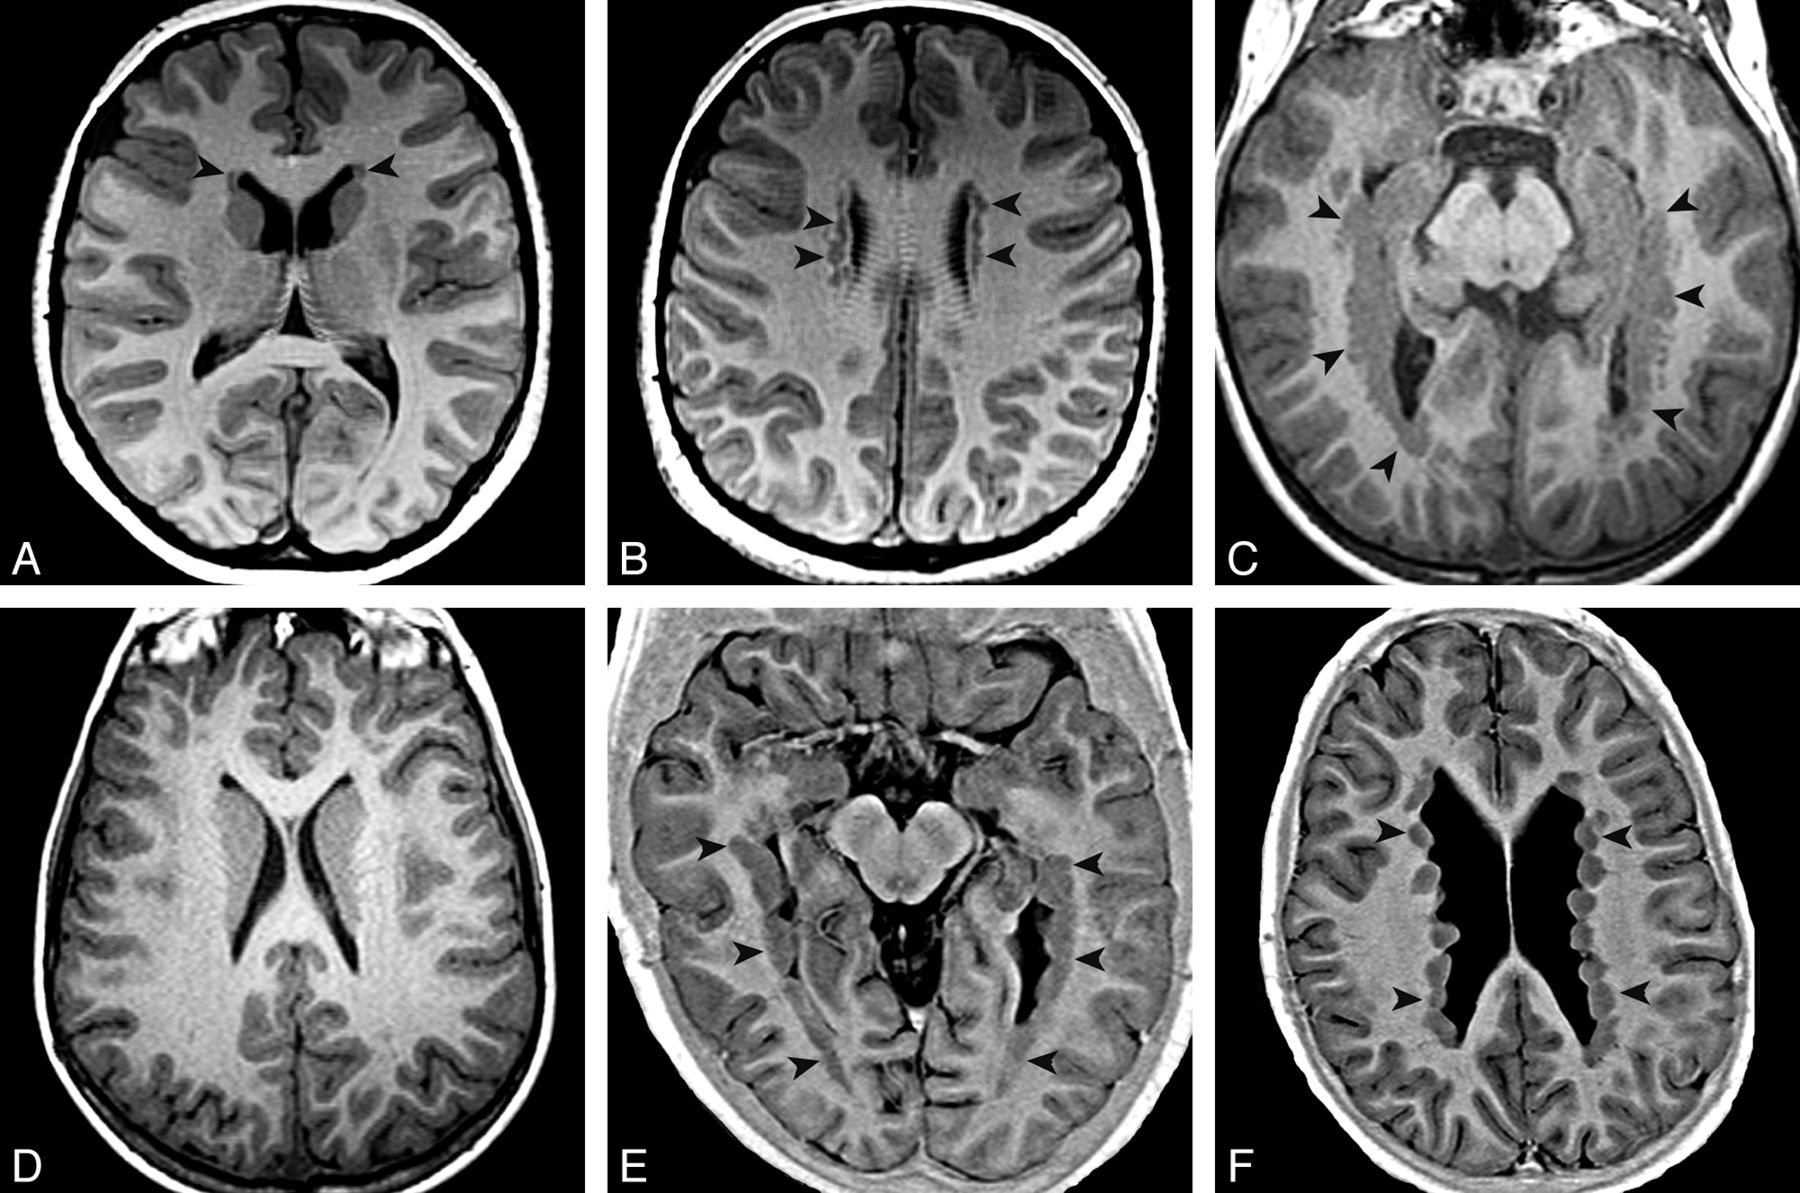

The number, side, and location of the nodules of PNH were recorded for each patient. By number, they were classified as ≤5 nodules (group 1), 6–10 nodules (group 2), or >10 (group 3). Unilateral PNH (uPNH) versus bilateral PNH (bPNH) was recorded. PNH location was classified by the ventricular segments affected (Fig 1). Those in the frontal horns and/or bodies of the lateral ventricles were classified as aPNH, while pPNH referred to heterotopia located only in the trigones, temporal horns, or occipital horns of the lateral ventricles. Heterotopia located in all of the ventricular segments was classified as dPNH. If heterotopia were few (group 1) and scattered, they were classified as isolated and not included in further analyses. We did not separate a FLNA-like pattern (PNH in the frontal horns, bodies, trigones, and occipital horns but not in the temporal horns) as separate from other patterns because genetic analyses were not available in most of our patients and the associated findings of megacisterna magna and mild vermian hypoplasia are well-described.17,18

PNH main patterns evaluated with T1 inversion recovery–weighted image. Arrowheads show locations of heterotopia. Axial images show an aPNH pattern with nodules restricted to the frontal horns (A) and bodies (B). Axial images demonstrate a pPNH pattern. Nodules are lining trigones and temporal and occipital horns bilaterally (C), sparing the frontal horns and bodies (D). E and F, Axial images show a dPNH pattern with nodules lining all of the walls of the lateral ventricles.